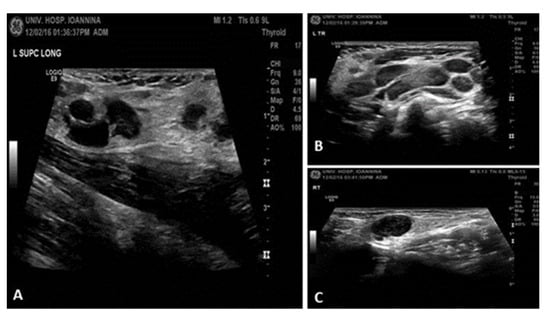

Ultrasound: multiple enlarged, hypoechoic, rounded cervical and supraclavicular lymph nodes (Figure 2).

Ultrasound findings: (A) In the supraclavicular regions, multiple enlarged lymph nodes are also revealed that locally converge. Some of them appear hypoechoic and rounded; the largest is on the left with a maximum diameter of ~1.3 cm. (B,C) In the cervical regions and within the parotid glands, more commonly on the left, multiple enlarged lymph nodes of maximum diameter up to 2 cm are observed, which in some areas converge with an oval morphology and normal architecture.